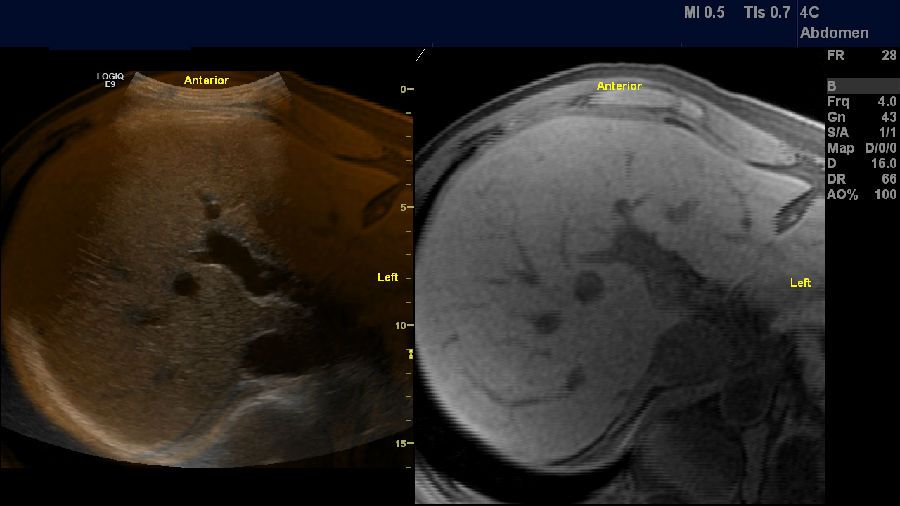

肝脏容积导航融合成像